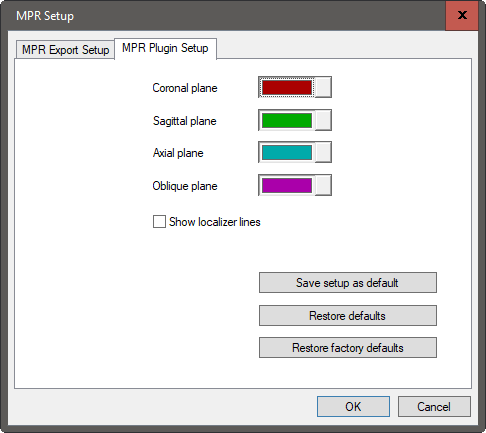

Settings for the colors of the orthogonal image frames can be configured in the MPR Plugin Setup page. From this page the user can define the desired color and enable or disable color-coordinated localizer lines.